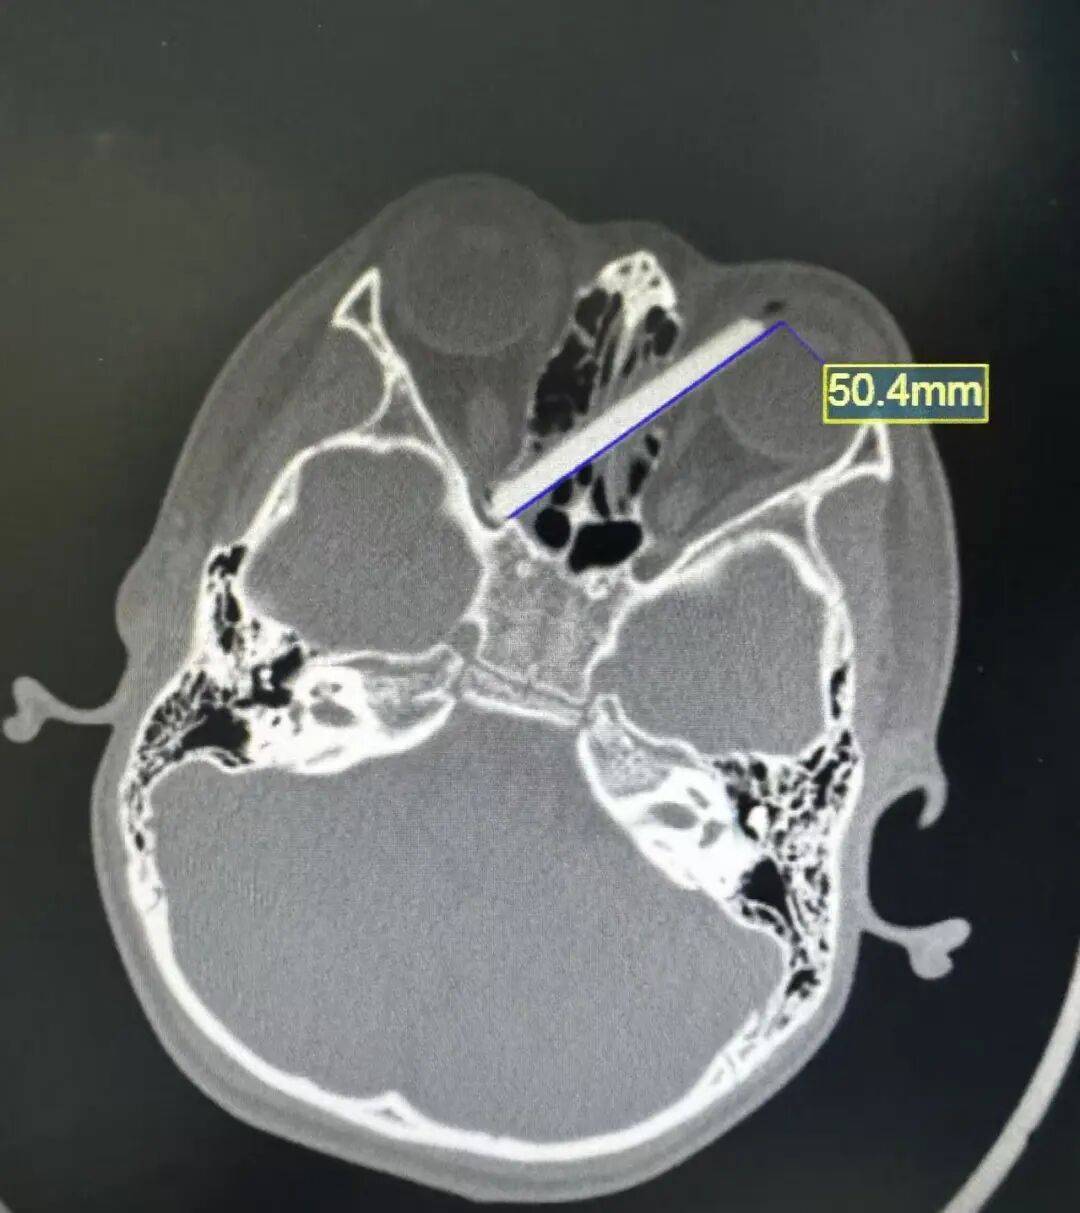

接诊医生当即安排男孩进行急诊CT检查。CT检查结果显示:失踪的那截筷子,的确插进了孩子的左眼。断筷径直贯穿双侧鼻窦,另一端深深嵌入右眼视神经管附近。

据了解,筷子紧贴着孩子的左眼球壁,稍有偏差就可能导致左眼球破裂;而筷子的另一端则紧紧抵住右眼的视神经管,一旦视神经受损,孩子随时面临失明的风险。筷子不仅进入了双侧眼眶,还插入了鼻子。除了视力问题,眼眶周围和鼻窦内血管密布,且紧邻大脑,如果不及时手术取出筷子,很可能引发血管破裂、大出血甚至颅内感染。